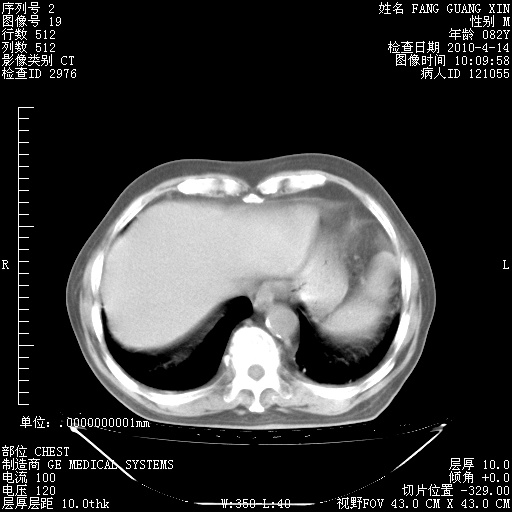

4月14日肺部CT

楼主| 发表于 2010-4-28 16:51 | 显示全部楼层

楼主| 发表于 2010-4-28 16:53 | 显示全部楼层

肺部CT平扫未见异常。